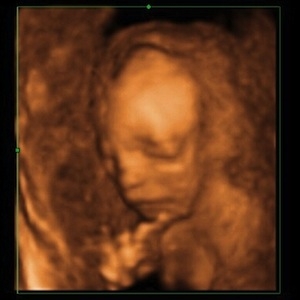

Noch mehr Bilder? Jetzt reichts erstmal. - Tagebücher aus der Schwangerschaft von Kristin aus Jena